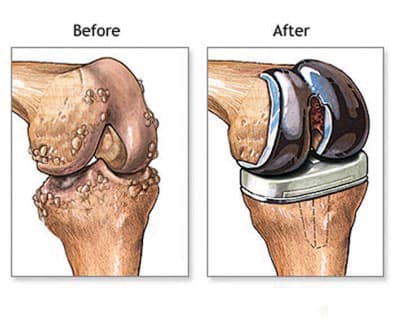

تستبدل المفاصل الطبيعية عند تلف وزوال المادة الغضروفية في المفصل نتيجة التهاب المفصل العظمي أو أحد أنواع التهابات العظم الروماتيزمية، وأكثر الأنواع شيوعاً هو "الاحتكاك، ويعد المفصل الصناعي الطريق الأمثل لتحسين الحركة للتخلص من الآلام واستعادة استقلالية القدم، وجراحة استبدال المفصل الصناعي أكثر الطرق فعالية للتخلص من الآلام المبرحة في المفصل، ويتم ذلك بواسطة استبدال الأسطح التالفة، وأيضاً عن طريق تعديل استقامة القدم وتحسين آلية الركبة، ما يسمح للعضلات التي أضعفها الاحتكاك على استعادة قوتها، وجراحة استبدال المفصل هي خصوصاً للمرضى الكبار السن.

وفي بعض الأحيان لمتوسطي العمر وأن زراعة المفاصل من أكثر العمليات التي أثبتت نجاحها في الوقت الذي زادت فيه الخبرات بشكل كبير، وهنا يأتي دور العمل الجراحي، حيث يتم تغطية السطوح المفصلية المتعرية بقطع معدنية وبلاستيكية تشابه في شكلها المفصل الطبيعي، وبهذا تخف معاناة المريض من الألم ويستعيد المفصل قدرته على الحركة بشكل شبه تام يسمح للمريض بأداء الكثير من النشاطات اليومية في حياته.

لقد أثبتت المفاصل الصناعية نجاحها، فقد تطورت تطوراً سريعاً خلال السنوات العشر الماضية ولقد بدأ استخدامها منذ 30 عاماً، ونظراً لما يعترض مفصل الركبة من إصابات تؤدي إلى تلفه فقد حصلت تطورات كثيرة على المفصل الصناعي للركبة خلال السنوات الخمس الماضية، والمفصل الصناعي للركبة يلائم صغار السن وأكثر ثباتاً. وإن أكثر مضاعفات جراحة الركبة هي الالتهابات، حيث تبلغ نسبة هذه المضاعفات 1 في المائة فقط في المراكز الطبية المتميزة، وهي نسبة ضئيلة ولكنها إن حدثت فهي مشكلة كبيرة، عندها قد نضطر إلى نزع المفصل الصناعي ونضع مكانه مضاداً حيوياً على شكل طبقة طبية، وقد يخضع المريض لفترة من العلاج قبل وضع المفصل الصناعي من جديد، كما تشمل بعض المضاعفات الأخرى كجلطات الدم في القدم التي من الممكن السيطرة عليها بشكل فاعل بالتحرك المبكر وباستخدام الأسبرين ومسيلات الدم الأخرى، وجعل المريض يتحرك مبكراً لمنع حدوث الاحتقان في الرئتين.

ومفصل الركبة من المفاصل المهمة التي تقوم بدور عظيم في حياة الإنسان، فعليها يتم حمل الجسم "إضافة إلى المفاصل الأخرى في الأطراف السفلية"، وهو مفصل دقيق ومعقد، وما يميزه من الناحية التشريحية عدم وجود طبقة عضلية سميكة تغطيه، وهذا ما يجعل عملية إجراء المفاصل الصناعية من الناحية العملية أمراً ليس بالهين، ويحتاج إلى الكثير من الخبرة والدقة لإجرائه، فهناك الكثير من النقاط التي يجب مراعاتها أثناء العمل الجراحي إلا أن التطورات الأخيرة في مجال المفاصل الصناعية ووجود نخبة من الجراحين وازدياد الخبرات في ذلك جعل نتائج العمليات أفضل بكثير من ذي قبل، وأصبح بإمكان الكثير من المرضى ممارسة حياتهم بشكل قريب جداً إلى المستوى الطبيعي، وعلى المريض أن يستشير طبيبه كي يساعده على اتخاذ القرار واللجوء إلى الحل الجراحي.